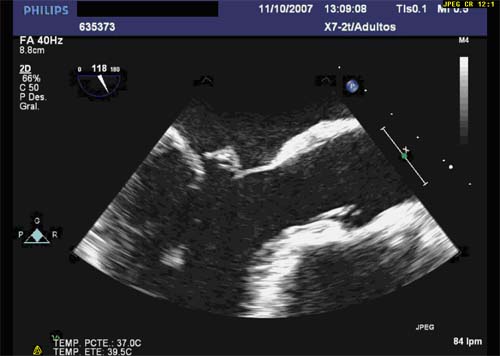

MITRAL VALVE LEAFLETS There are two leaflets—anterior mitral leaflet (AML) and posterior mitral leaflet (PML). • Anterior mitral leaflet: AML is in continuity with the evaluate the Mitral Valve3 While performing TEE examination, it is important to under- ... Access Doc